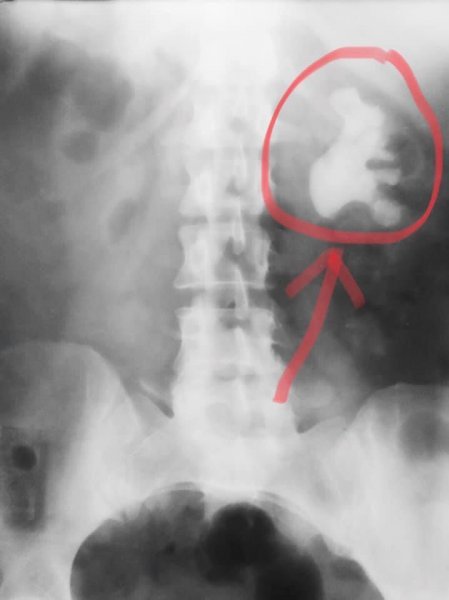

П'ять нирок знову почнуть функціонувати, а 5 щасливих пацієнтів позбавляться від страждань, спричинених величезними каменями. Рекордсменом став величезний кораловидний камінь правої нирки (на фото). Технічно надзвичайно складний випадок.